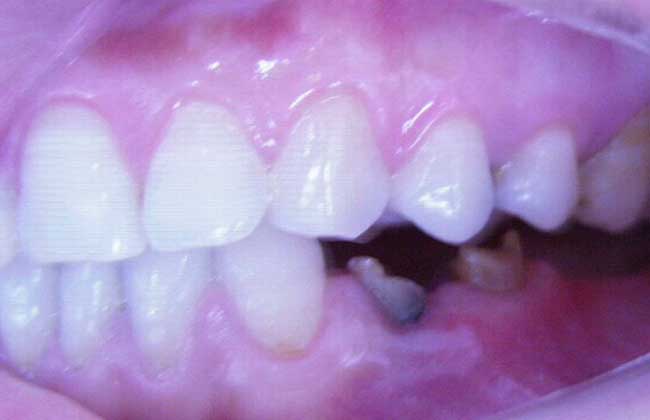

2、口腔情况:不同的人口腔情况不同,患者如果骨量充足、牙龈条件好的话,种植牙寿命就会长些。如果自身牙齿条件不好,寿命也自然短些。